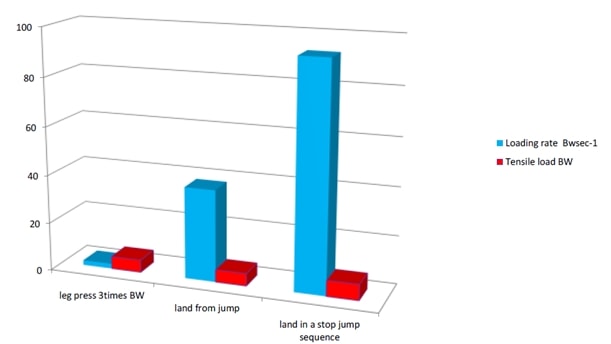

3. Степента на натоварване на сухожилията вероятно обяснява защо тендинопатията се свързва с повтарящ се цикъл на разтягане и съкращаване (SSC), а не с тежки натоварвания. SSC възниква по време на всяка дейност, която изисква сухожилието да съхранява и освобождава енергия като пружина. Всичко останало е лесно за сухожилието, например ексцентрични движения, голяма тежест. Скоростта на зареждане се изчислява в BW/sec. Ето два примера за пателарното и ахилесовото сухожилие при различни дейности. Така че най-високата степен на натоварване на пателарното сухожилие е при приземяване в последователност на скок със спиране, като например при баскетбола или волейбола, докато при натискане на крака с 3 пъти по-голямо телесно тегло степента на натоварване е много ниска.

Тежките упражнения с бавно съпротивление са лесни за сухожилията. Упражненията за разтягане и съкращаване са трудни за сухожилията.

Натоварване на пателарното сухожилие на опън и скорост на натоварване при типични дейности: